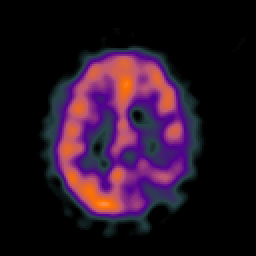

SPECT TC Study #5 -- Slice #36

[Home][Help][Clinical][Tour 1][Tour 2][Tour 3] Slice 36